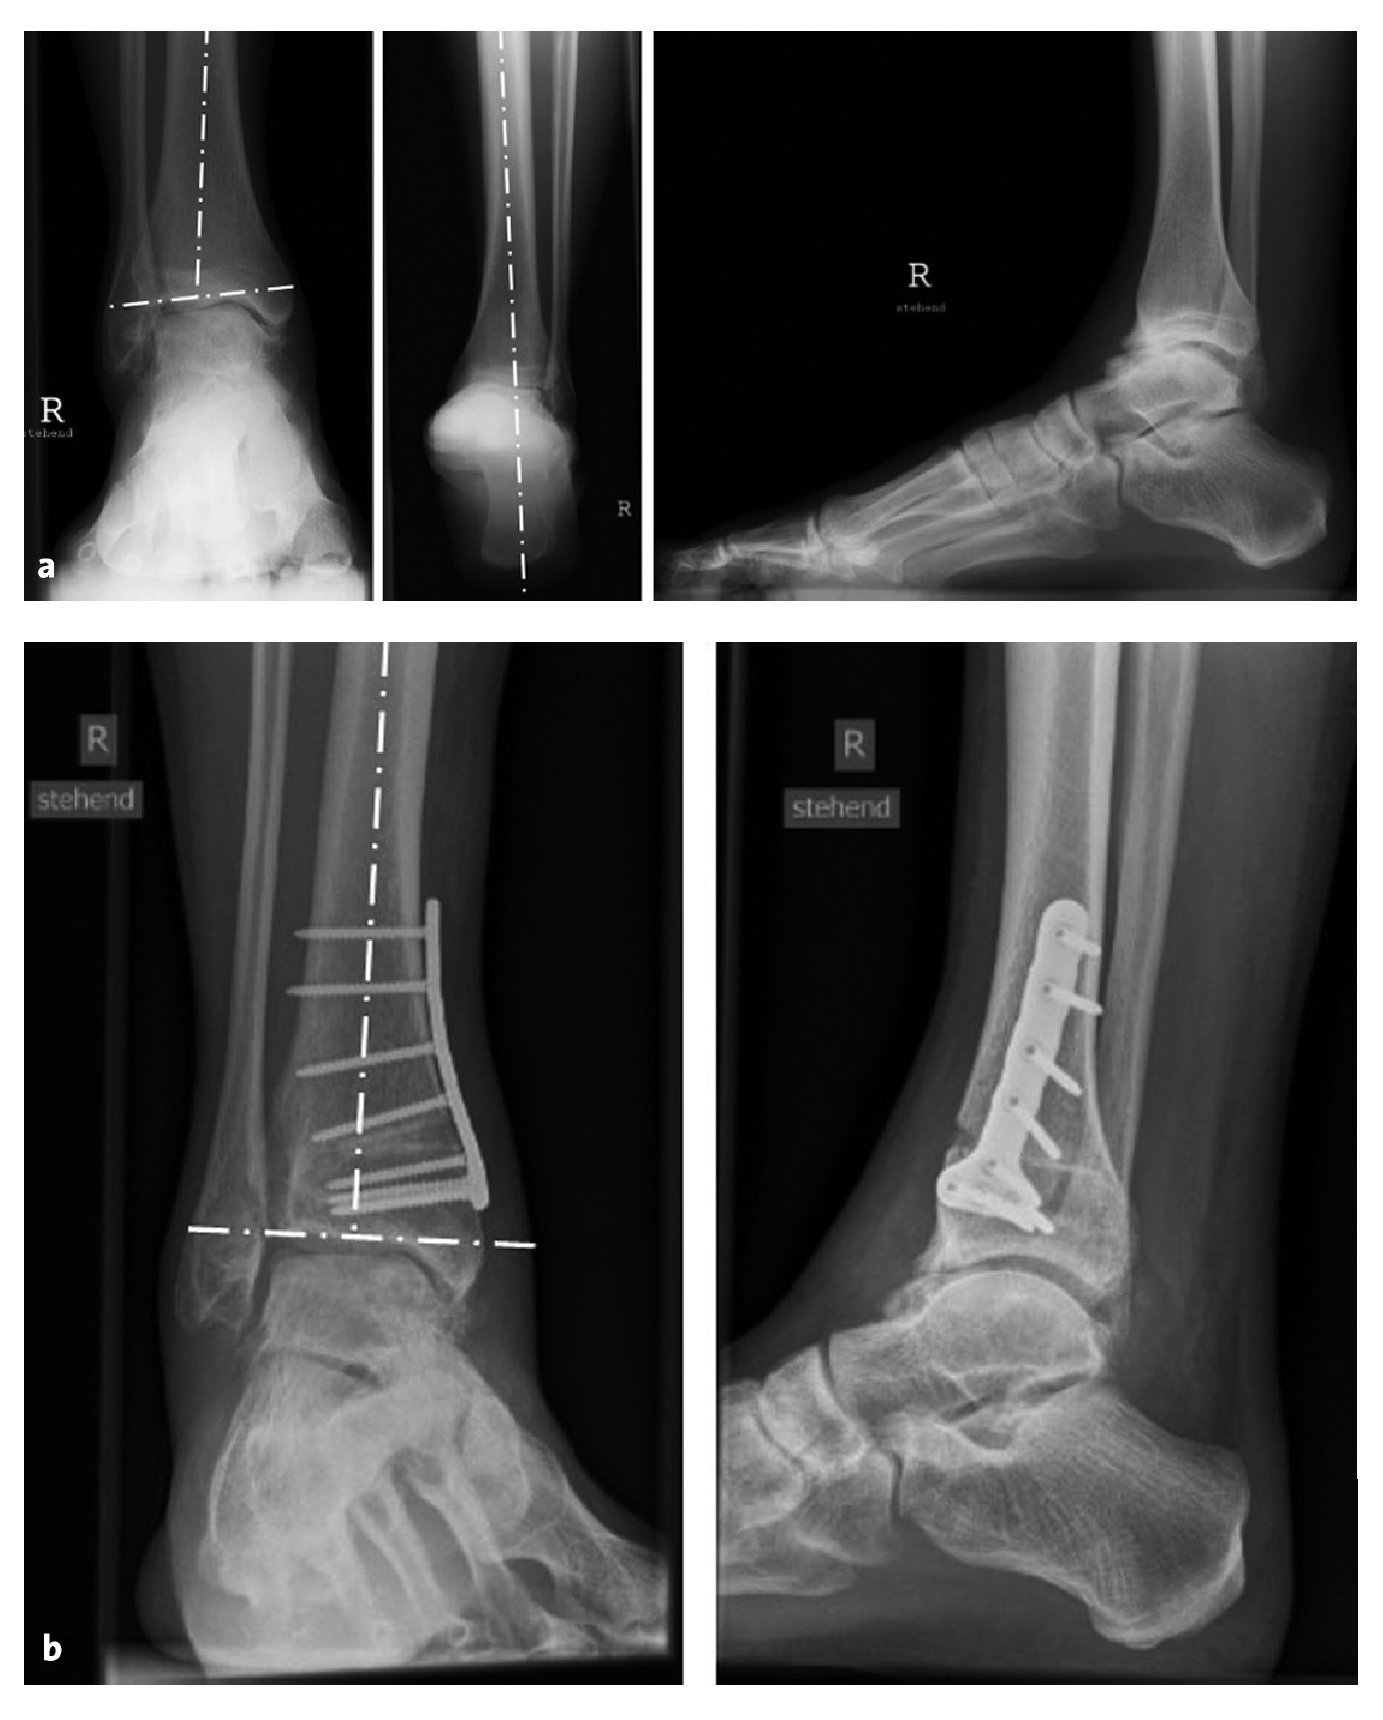

A lo largo de 5 años (3-10,5 años), se realizaron exploraciones clínicas y radiográficas de seguimiento a un total de 12 pacientes que tenían deformidad en varo de la articulación tibiotarsiana superior (figs. 14a y 14b). Se observó una disminución del dolor de 7 (4-10) a 3 (1-6) en una escala analógica visual7 (EAV) (p = 0,0001), como refieren otros autores1,13,14. En todos los pacientes se observó una mejoría de la capacidad funcional con una mayor capacidad deambulatoria y mayor movilidad de la articulación tibiotarsiana superior (33º [5-55º] en el preoperatorio en comparación con 39º [25-50º] en el postoperatorio), así como una mayor actividad física7, de acuerdo con otras publicaciones1,14,15. El índice de Takakura (véase la tabla 2) mostró un retroceso radiográfico de los signos de artrosis (de 2,2 [1-3] en el preoperatorio a 1,4 [1-2] en el postoperatorio) en un total de nueve pacientes (75%). En tres de los pacientes, el índice de Takakura no se modificó.

Figuras 14a y 14b. a) Radiografía de un paciente varón de 29 años con una desviación en varo aislada de la articulación tibiotarsiana, que también se observa en la lateralización de la radiografía de Saltzman. b) Radiografías 3 meses después de la osteotomía en cuña abierta medial de la tibia distal con normalización del ángulo de la articulación tibiotalar.